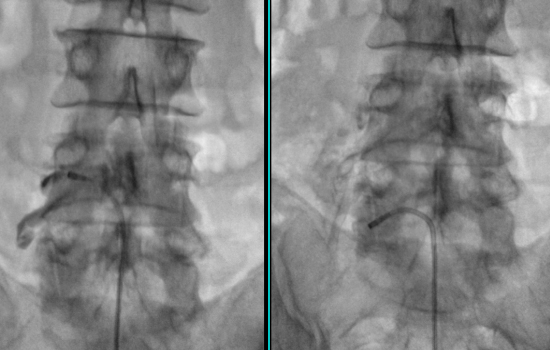

경추 혹은 요추 디스크가 파열되는 등의 심한 손상이 생겼을 때, 신경 주변의 유착을 박리하고 노폐물을 세척하는 시술 입니다. 꼬리뼈 쪽으로 지름 1mm 특수 카테터 관을 삽입하여 디스크나 협착증이 있는 신경부위에 신경 부종이나 유착을 제거하고 염증이 발생한 부위에 약물을 직접 투여 합니다.